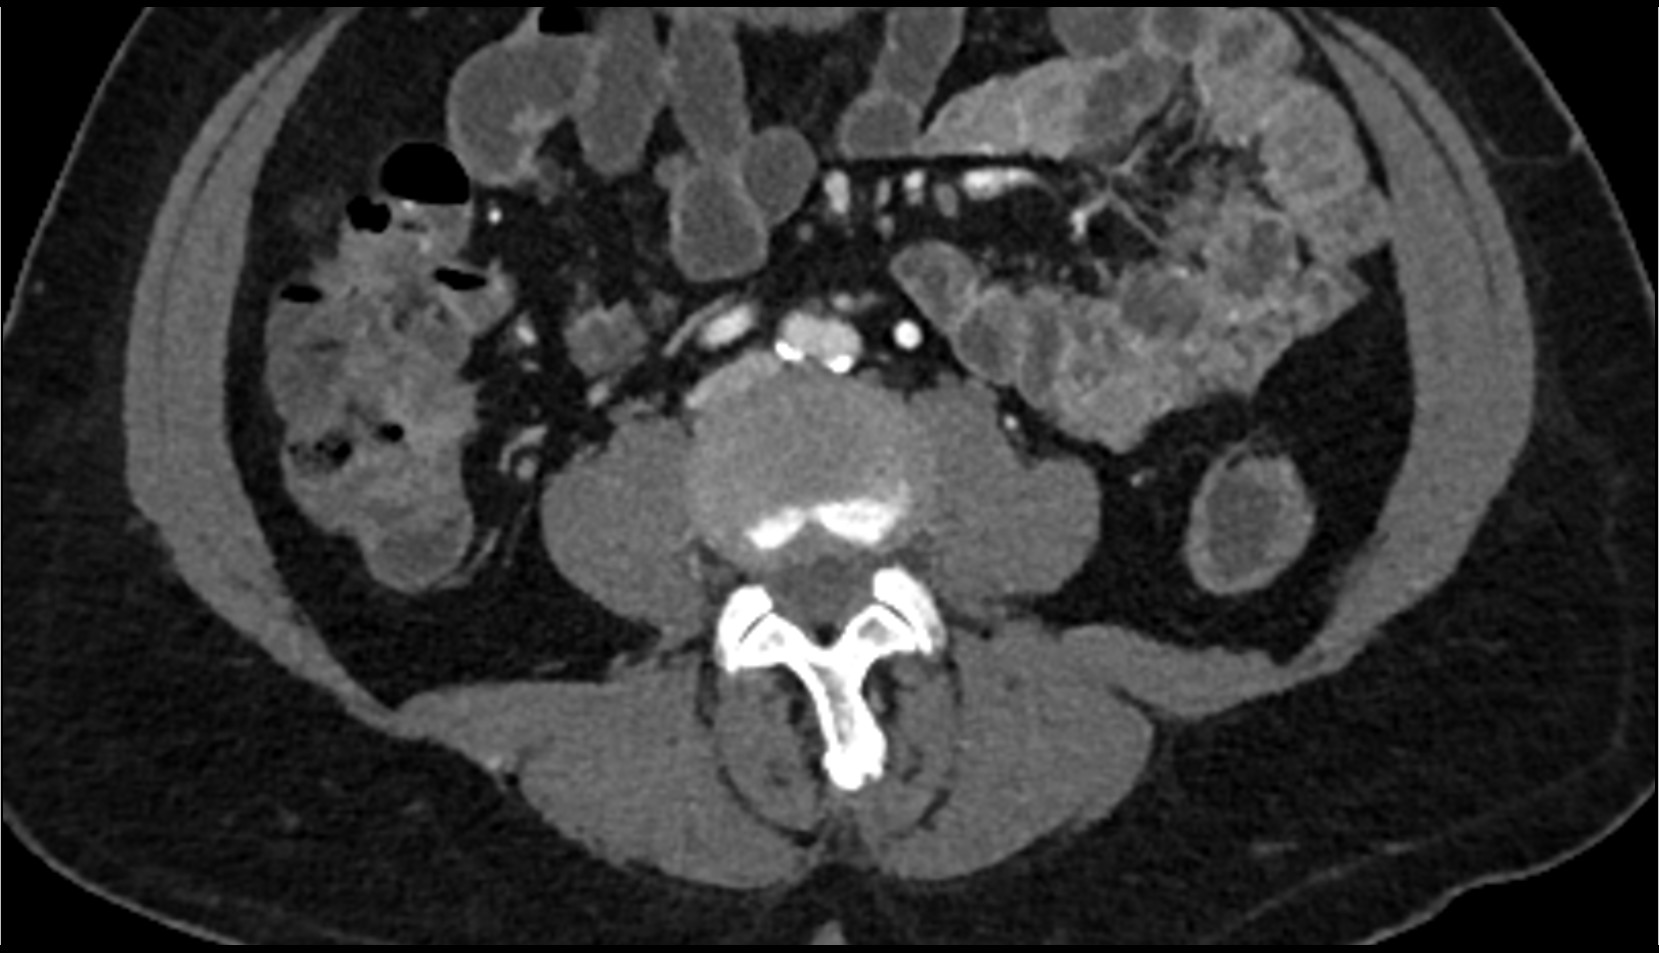

- Psoas major muscle

- Quadratus lumborum muscle

- Iliacus muscle

- Aortic bifurcation

- External iliac artery

- Internal iliac artery

- common iliac artery

- Common iliac vein

- Right kidney

- Left kidney